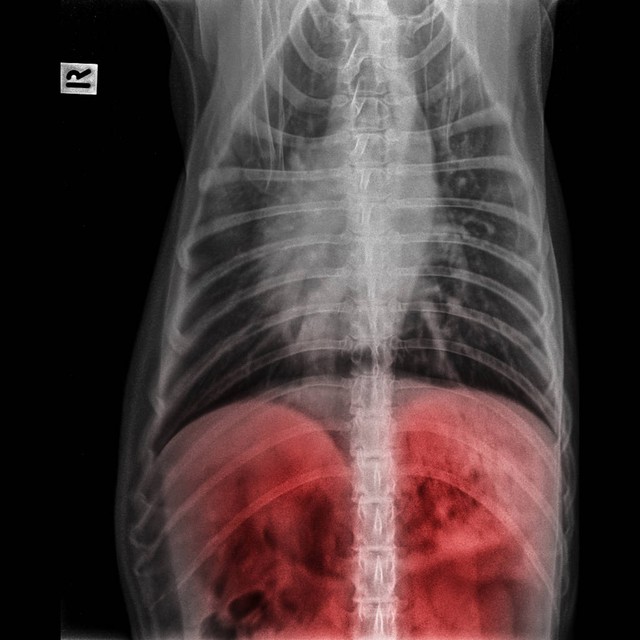

后来经过病友的介绍,赵先生的家人带着他来到武汉找到肝病专家费雁进行就诊。费主任看了一下赵先生带来的化验单,上面显示乙肝大三阳,肝功能全部异常,谷丙、谷草转氨酶都200多,白蛋白22,病毒量是6次方,B超提示是肝硬化,腹腔有积液,深度在3cm左右,确诊为肝硬化失代偿期。

赵先生说他从今年过完年就开始感觉浑身总没劲,食欲一直不好,体重照比年前,瘦了10多斤,而且右边肋骨里头用有隐隐作痛的感觉,然后到老家医院一查,没想到查出肝硬化了,还有腹水。